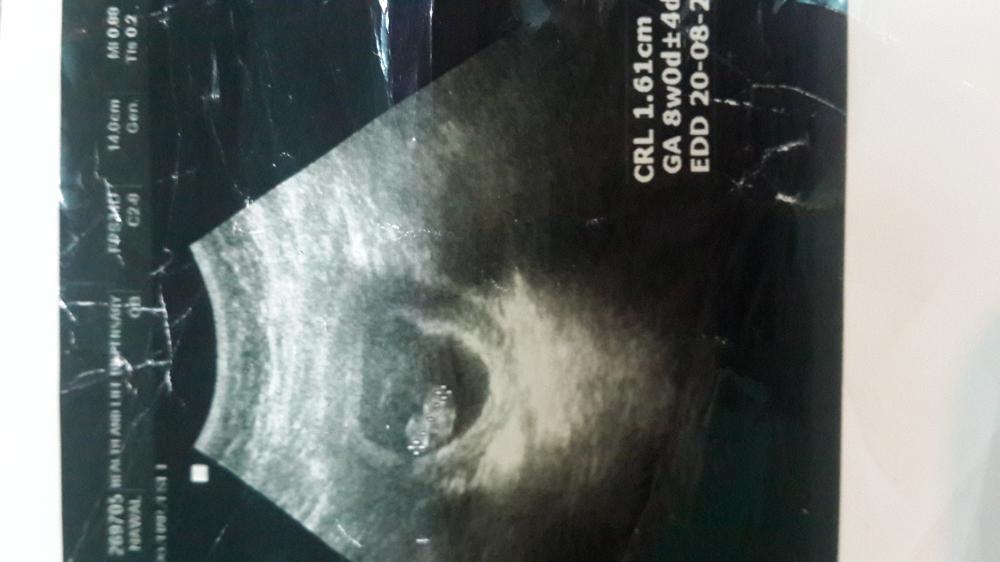

المعذرة صاحبة الموضوع شوفوا سوناري وارجوا من العضوة رنا هنا تعطيني توقعها مع العلم ان هالسونار قديم وانا الان في الشهور الوسطي وعرفت جنسه

المعذرة صاحبة الموضوع شوفوا سوناري وارجوا من العضوة رنا هنا تعطيني توقعها مع العلم ان هالسونار قديم وانا الان في الشهور الوسطي وعرفت جنسهالمعذرة صاحبة الموضوع شوفوا سوناري وارجوا من العضوة رنا هنا تعطيني توقعها مع العلم ان هالسونار...

اعتقد ولد والعلم عند الله